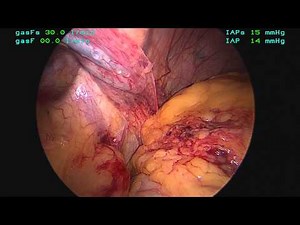

Hallinan - Diaphragm Plication

Surgery - Right Hemidiaphragm

Surgery - Diaphragm Surgery

Procedure - CXR PA and Lateral